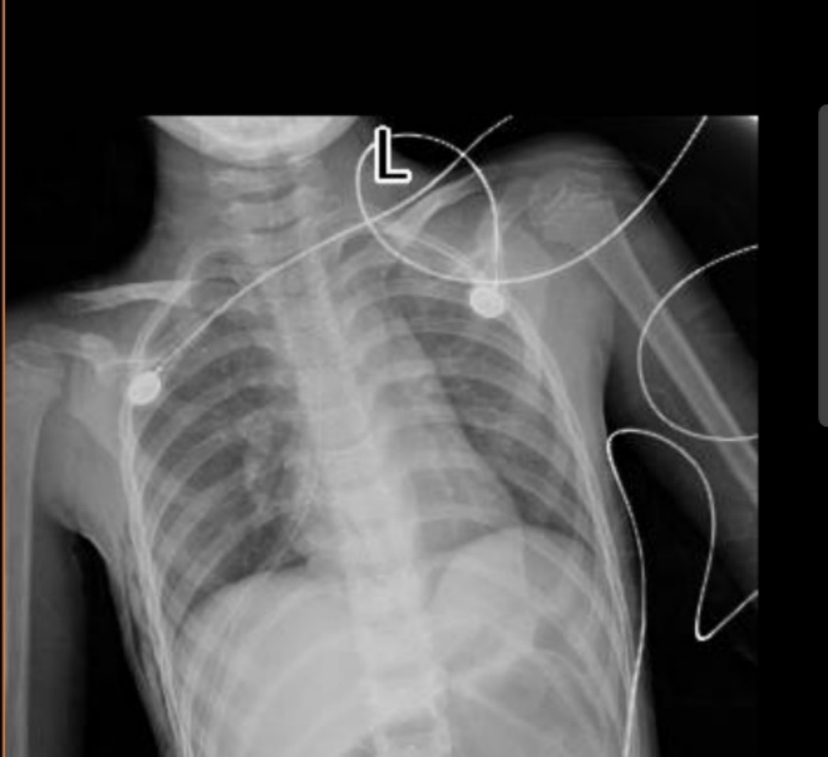

7岁女孩小优优还在妈妈肚子里的时候就被医生发现她的胸腔里长了颗“小豌豆”,诊断是后纵隔占位,从优优出生开始,这颗“小豌豆”也在她身体里悄悄地生长着。优优最开始倒是没有明显的不舒服,与其他小朋友一样,觉睡得好,饭也吃得香,优优妈妈看她健康活泼,也不想孩子小小年纪就被推进手术室,怕给她留下心理阴影,就没去做手术。一段时间过去,优优吃饭吞咽时总感到有些阻碍,今年年初优优妈妈带她复查,发现优优那颗纵隔肿瘤近年来逐渐增大,已长大到5*6厘米,柠檬大小,位于心脏后方,跨越左右胸腔和部分腹膜后,与食道关系密切,压迫了食管,使得食管变窄,情况不好,唯一的出路就是手术切除。

复查结果令优优妈妈很担忧,2个月前的一个周三下午,优优妈妈带着优优来到了深圳市人民医院名医门诊,找到王光锁教授,为小优优量身定制个体化手术方案。手术时机不宜继续推迟,可以考虑切除了。但要怎么做呢?怎样才能以最小的代价、最小的创伤,精准地切除潜伏在后纵隔狭窄间隙里、跨越左右胸腔和胸腹腔的肿瘤呢?